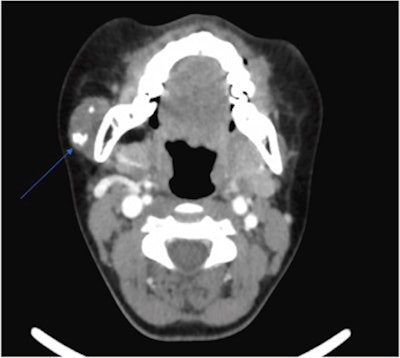

Attempts to conduct an ultrasound-guided biopsy failed because the needle wouldn't penetrate the lesion. Therefore, the patient underwent computed tomography (CT) and magnetic resonance imaging (MRI) of her neck, which showed an unusual lesion with calcification that appeared toothlike near the border of the girl's parotid gland and masseter muscle, the authors wrote.

Due to the lesion's unknown origin and concerns that it may be a possible neoplasm, a multidisciplinary team recommended an excision biopsy. The girl underwent a superficial parotidectomy to include the mass, which had multiple phleboliths clumped inside.